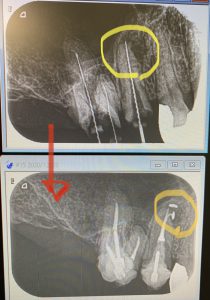

1ヶ月半程、根管の殺菌消毒して本日根管充填(最終的な根管充填材)へ。

オッと‼︎‼︎‼︎、、(´⊙ω⊙`)

根管の尖端付近が枝分れしています

このようにな『側枝』が空洞化していると、根管の感染が再燃する一因になります。

普通の根管充填方法ではストレートの本管しか充填材は入りません💦

このような湾曲した細い枝に充填出来るのは、NT(ニッケルチタンファイル)オブチュレーションシステムを採用しているからです。

C Tでも分かりますね